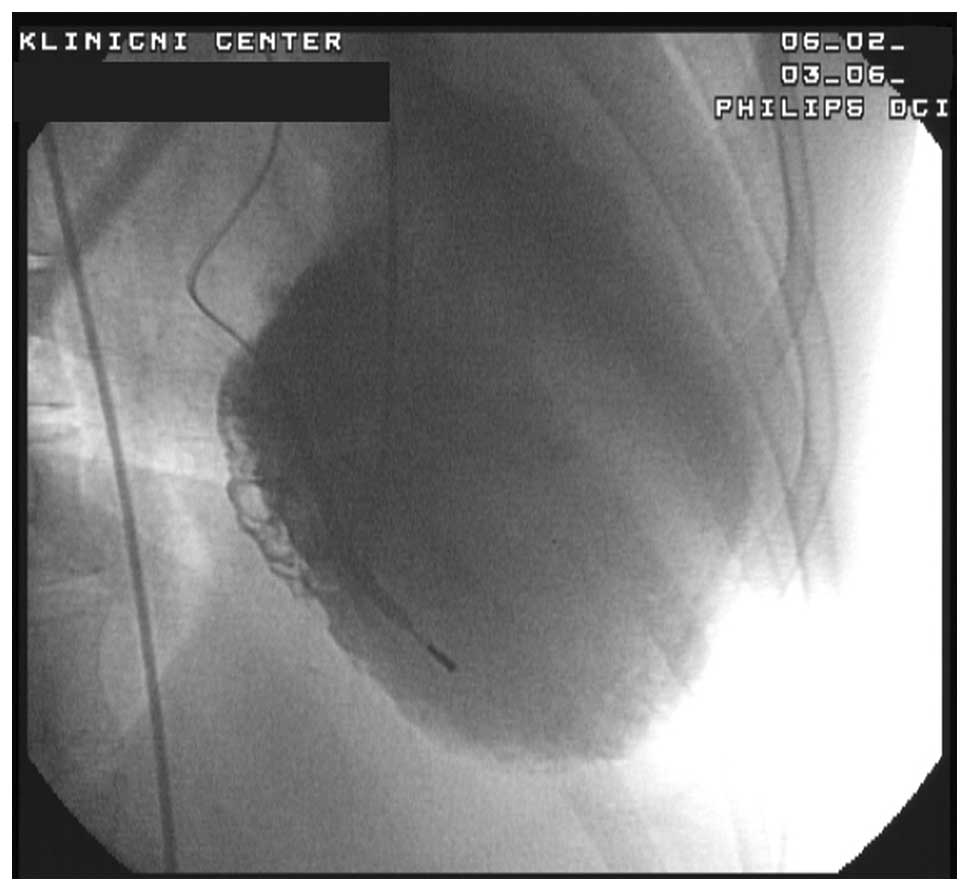

Dilated cardiomyopathy and ovarian dysgenesis in a patient with Malouf syndrome: A case report

Malouf syndrome is a rare congenital disorder involving the heart, genitalia, skin and skeletal characteristics. In the present study, we report on the sporadic case of a young female with dilated cardiomyopathy, hypergonadotropic hypogonadism, a small chin, bilateral blepharoptosis, marfanoid elongated fingers and hypothyroidism. Malouf syndrome may be caused by heterozygous mutations in the lamin A/C (LMNA) gene. Genetic analyses and autopsy were performed. In spite of the patient's features, sequence analysis of the coding region of the LMNA gene including exon‑intron boundaries identified only one benign polymorphism: homozygous silent variant 1698C>T (H566). There is a possibility that the sequence analysis may have not detected intronic mutations or mutations in portions of the 5'- and 3'-untranslated regions, which would confirm the clinical diagnosis.

Figure 1

Figure 2

Figure 3

Figure 4

Figure 5